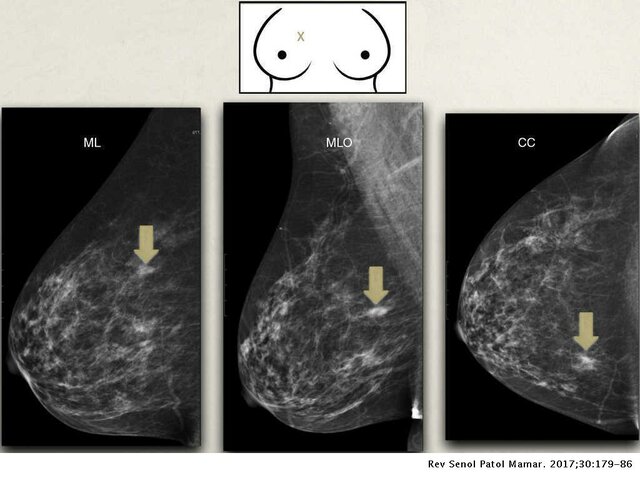

• Foto Mamográfica (2000)

Foto Mamográfica (2000)

Es un diagnóstico por medio de una imagen de rayos X de la glándula mamaria, mediante aparatos denominados mamógrafos. Estos tienen tubos de emisión de rayos X especialmente que son especialmente adaptados para conseguir la mejor resolución que sea posible en las estructuras fibroepiteliales internas de la glándula mamaria.